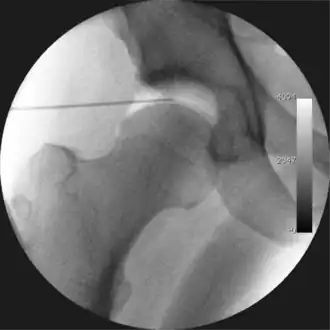

![]() Intraoperative fluoroscopic image during an arthroscopic resection of a cam lesion of the femur. The upper instrument is the arthroscope (viewing device), while the lower is the high-speed burr used for reshaping the bone. |

Figure 3. Fluoroscopic picture showing a mild amount of distraction of the hip before insertion of any instruments -

Figure 4. A needle is passed into the joint, breaking the 'suction seal', and allowing further distraction of the hip joint with minimal extra traction -

The procedure is performed with the patient asleep (general anaesthetic) or under spinal anaesthesia. There are two widely used methods, one with the patient on their back (supine) and the other on their side (lateral decubitus). Which is used is down to the surgeon's preference. To gain access to the central compartment of the hip joint (between the ball and socket), traction is applied to the affected leg after placing the foot into a special boot. (See fig. 2) There is specifically designed equipment for this, although some surgeons use a 'traction table', initially designed to help in the operative fixation of broken thigh and lower leg bones. The amount of traction (or pull) needed is assessed with the help of fluoroscopy (low-dose portable x-ray). (See fig. 3) It is usually not possible to distract the ball from the socket with traction alone by more than a few millimetres. Once the surgeon is happy that they will be able to gain access to the hip joint (i.e. the ball will distract from the socket by a small amount), the patient is then painted with antiseptic and the surgical drapes applied.

The next step is to insert a fine needle under x-ray guidance into the hip joint. This breaks the 'suction seal' of the joint and allows further distraction if necessary (see fig 4). The surgeon wishes to see the ball move out the socket by approximately 1 cm, so that access to the hip joint can be achieved with minimal risk of damage to the joint surfaces. Most surgeons will inject fluid into the joint at this stage, again to ensure that there is enough space between the ball and socket for safe instrument access. This needle is then removed. The next step is placement of the 'portals', or the small holes made to pass instruments into the joint. This is achieved by again passing a fresh hollow needle into the joint under x-ray control, usually in a slightly different position. The reason for this is so the surgeon can ensure that the needle, and subsequent cannulae do not penetrate and damage the acetabular labrum or cartilage joint surfaces (see fig. 5). Again, surgeons will have their own preferences as to their preferred placement. Through this hollow needle, a long thin flexible guide wire is passed into the joint, and the needle is removed over it, leaving the guide wire in situ. A small cut in the skin is made around the wire, to allow for larger cannulae to be placed over the wire through the portal. The wire therefore guides the larger cannulae into the joint. The most common external diameters of cannulae used are between 4.5 and 5.5 mm. Once the surgeon is satisfied that the cannula is in the correct position, by a combination of feel and x-ray guidance, the guide wire can be withdrawn. Once the first portal is correctly placed, any further portals may be created once the camera is in position, to ensure that they are placed with minimal risk to the joint surfaces. This process can be repeated to gain as many points of entry to the hip joint as the surgeon requires, normally between two and four. Certain of these entry points will be used for the viewing arthroscope and others for operating instruments.